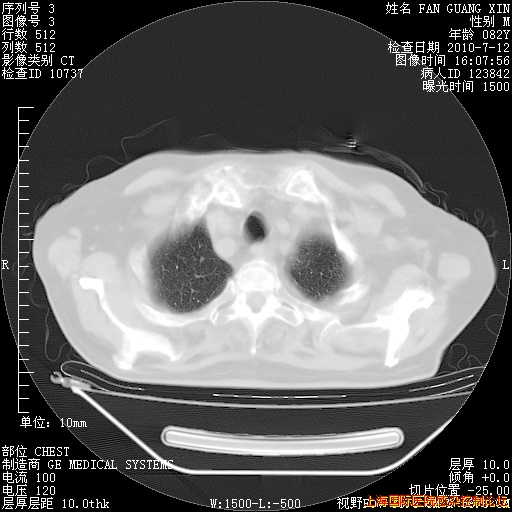

补发6月12日肺部CT肺窗

6月12日肺窗

整整相隔30天的肺部CT好像有所好转啊。甲强龙减量第3天,需要观察体温。

海管,自昨日你和我通完话后,不知您岳父消化道症状有无缓解?体温怎样?阅读7.12日胸部ct,个人认为目前激素治疗是有效的,甲强龙减量是适宜的。因在抗痨治疗,需密切观察肝功、肾功能和血常规。不过,老年、长期住院和大量使用激素,很担心菌群失调发生